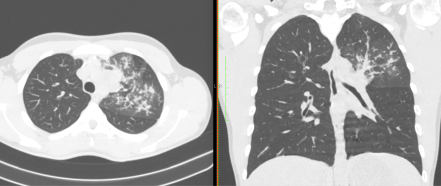

2. Наличие клинических проявлений, указанных в п. 1, в сочетании с характерными изменениями в легких по данным компьютерной томографии (КТ) (см. Приложение 1 настоящих рекомендаций) вне зависимости от результатов однократного лабораторного исследования на наличие РНК SARS-CoV-2 и эпидемиологического анамнеза.

- Изменения при КТ (рентгенографии), типичные для вирусного поражения (объем поражения минимальный или средний; КТ 1 - 2)

- Изменения в легких при КТ (рентгенографии), типичные для вирусного поражения (объем поражения значительный или субтотальный; КТ 3 - 4)

- Изменения в легких при КТ (рентгенографии), типичные для вирусного поражения критической степени (объем поражения значительный или субтотальный; КТ 4) или картина ОРДС.

КТ имеет высокую чувствительность в выявлении изменений в легких, характерных для COVID-19. Применение КТ целесообразно для первичной оценки состояния ОГК у пациентов с тяжелыми прогрессирующими формами заболевания, а также для дифференциальной диагностики выявленных изменений и оценки динамики процесса. КТ позволяет выявить характерные изменения в легких у пациентов с COVID-19 еще до появления положительных лабораторных тестов на инфекцию с помощью МАНК. В то же время, КТ выявляет изменения легких у значительного числа пациентов с бессимптомной и легкой формами заболевания, которым не требуется госпитализация. Результаты КТ в этих случаях не влияют на тактику лечения и прогноз заболевания при наличии лабораторного подтверждения COVID-19. Поэтому массовое применение КТ для скрининга асимптомных и легких форм болезни не рекомендуется.